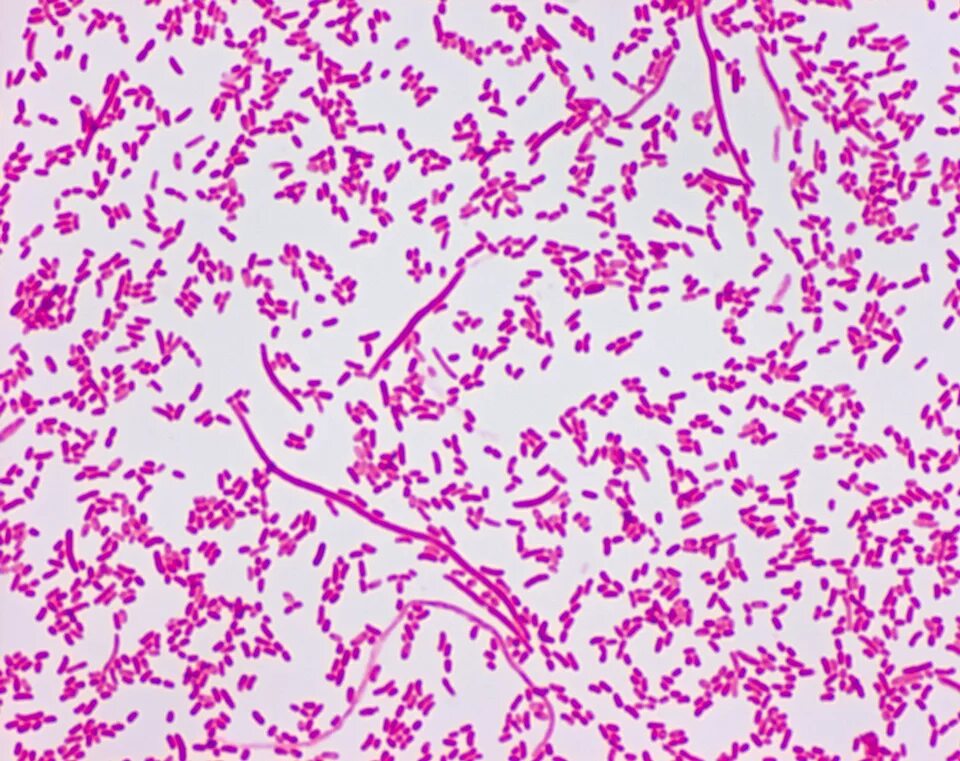

Sneathia spp